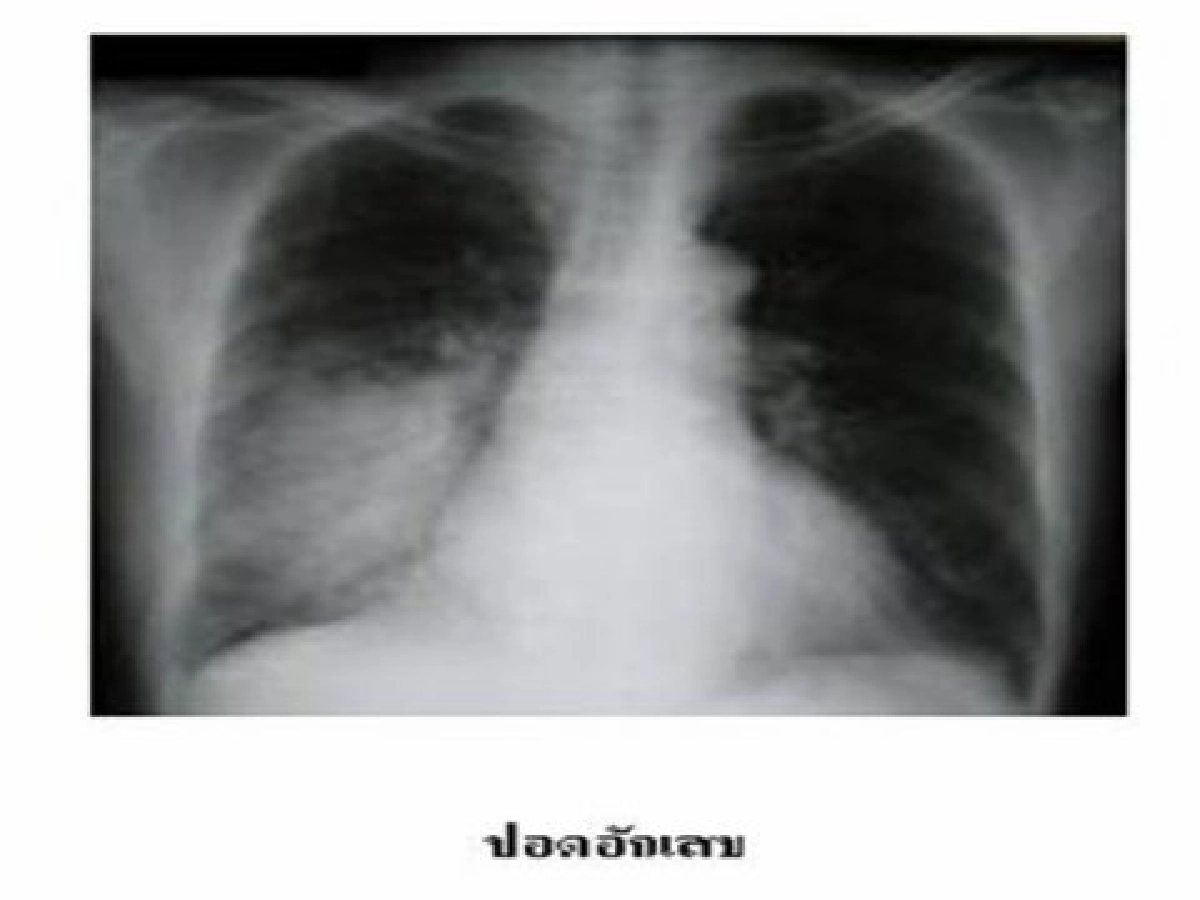

อาการและการวินิจฉัยโรค อาการสำคัญ คือ มีไข้สูง ไอ มีเสมหะ หอบเหนื่อย แต่ปอดอักเสบในผู้สูงอายุบางครั้งอาการไข้ไม่สูงชัดเจน โดยอาจมีอาการอื่น เช่น ซึม สับสน เบื่ออาหาร หนาวสั่น หรืออ่อนเพลีย ได้ ดังนั้น ถ้าผู้สูงอายุมีอาการผิดปกติไปต้องนึกถึงการติดเชื้อในปอดด้วย การวินิจฉัยโรคปอดอักเสบ จะอาศัยอาการร่วมกับการตรวจเอกซเรย์ปอดซึ่งจะพบลักษณะผิดปกติเป็นปื้นขาวบนเนื้อปอดปกติสีดำ